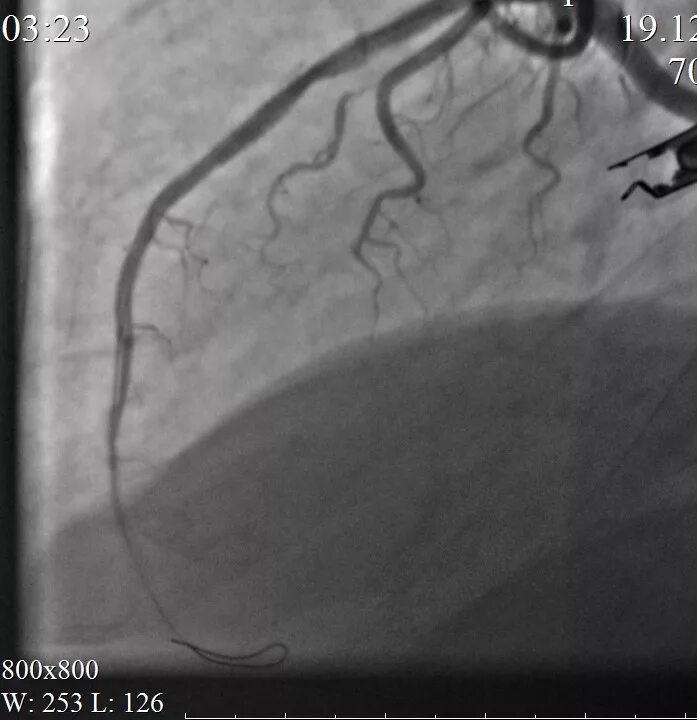

Стентирование срок больничного